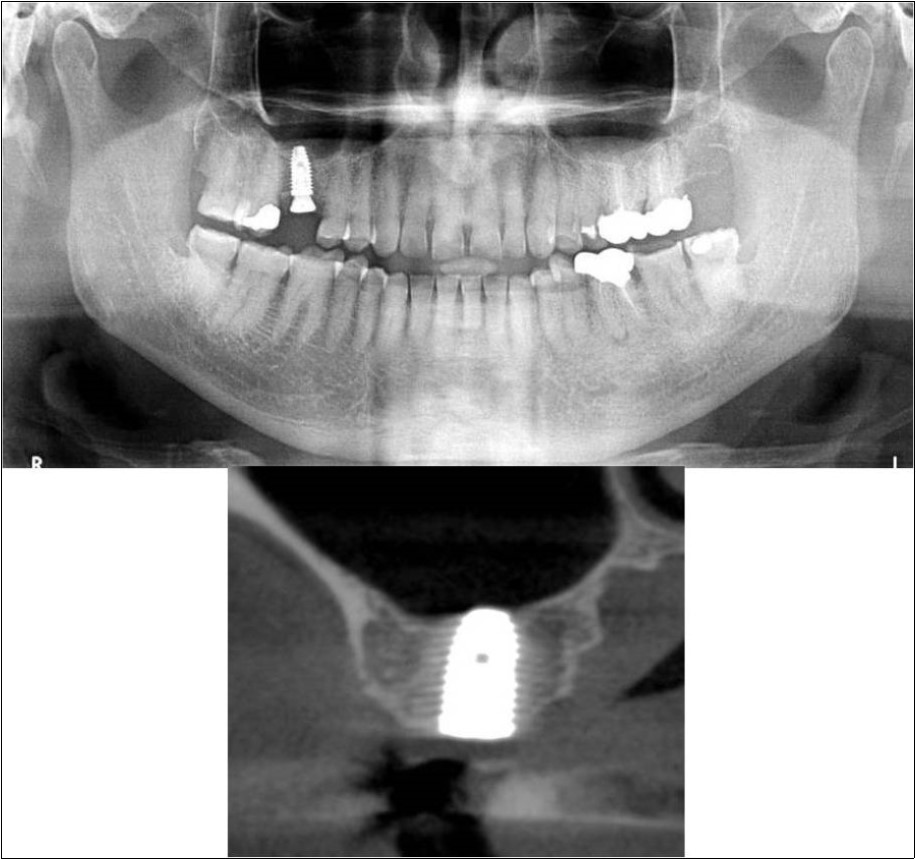

Treatment:

Patient underwent the procedure of indirect sinus elevation using sinus osteotomes in relation to 16 region. Calcium phosphosilicate putty was dispensed as the graft material through the crestal osteotomy site to maintain the elevated sinus membrane followed by placement of a dental implant measuring 5 x 10mm under local anaesthesia and strict aseptic protocols. The implant was allowed to osseo-integrate for a period of six months during which the patient was followed-up periodically and was assessed for peri-implantitis, crestal bone loss and mobility. At the end of 6 months, a repeat CBCT scan was advised to evaluate the increase in bone height. (Figure 11a,b, pre-treatment; Figure 12a,b, post-treatment)

Figure 11.(a,b) Pre-treatment OPG and cross section of CBCT showing residual alveolar bone height for Case No.3

Figure 12.(a,b) Post-treatment OPG and cross section of CBCT showing residual alveolar bone height for Case No.3;